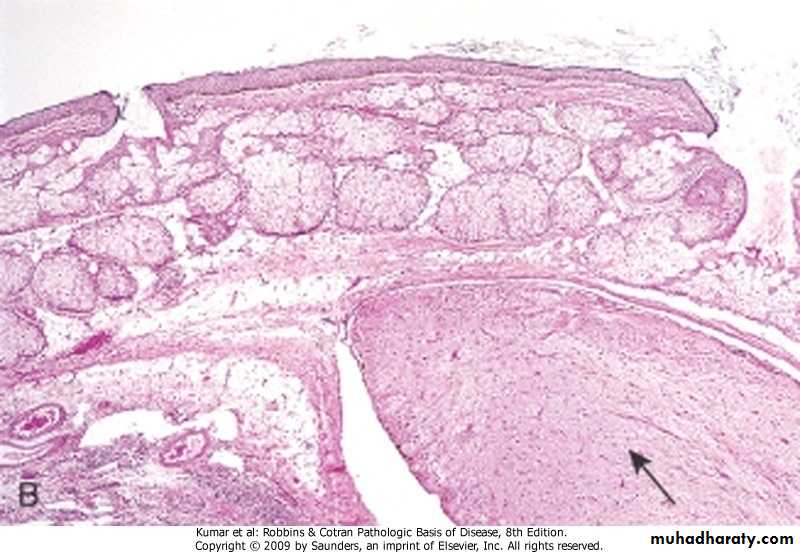

Colon, adenoma

Colon, polyp (adenoma)